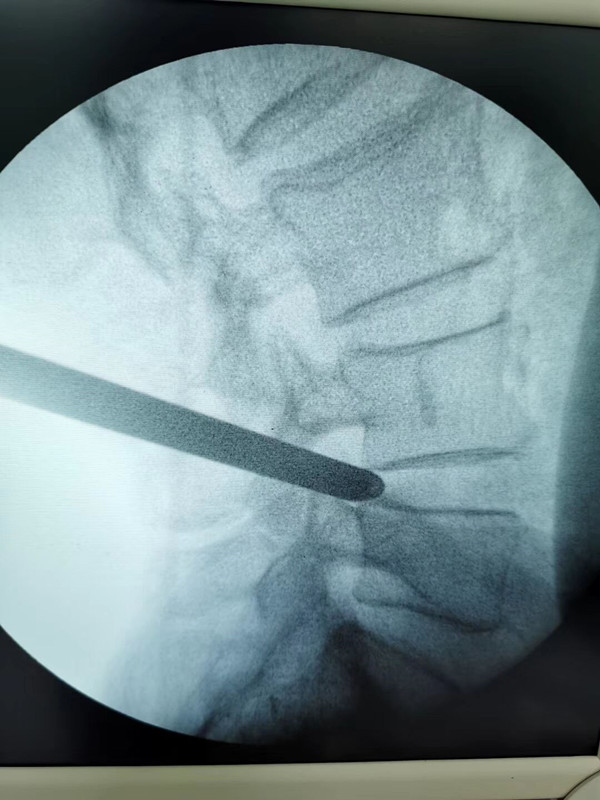

完善术前检查并经科室讨论后,刘勇主任认为患者手术指征明确,可以为江大爷进行椎间孔镜手术。在局麻下,开了一个6毫米小孔,刘主任为其进行了经皮椎间孔镜下髓核摘除术。术后,江大爷即刻解除了症状并于术后24小时下床,他对手术效果十分满意,一再感谢刘勇主任让自己摆脱了多年病痛的折磨。

刘勇主任介绍,椎间孔镜是目前临床应用越来越广泛的治疗间盘突出的一种微创的手术方式。它是一种可视微创手术,通过内窥镜可以清楚地看到发生压迫神经的突出物髓核组织,然后通过各类特殊的医用器械进行摘除,继而达到减压的目的。